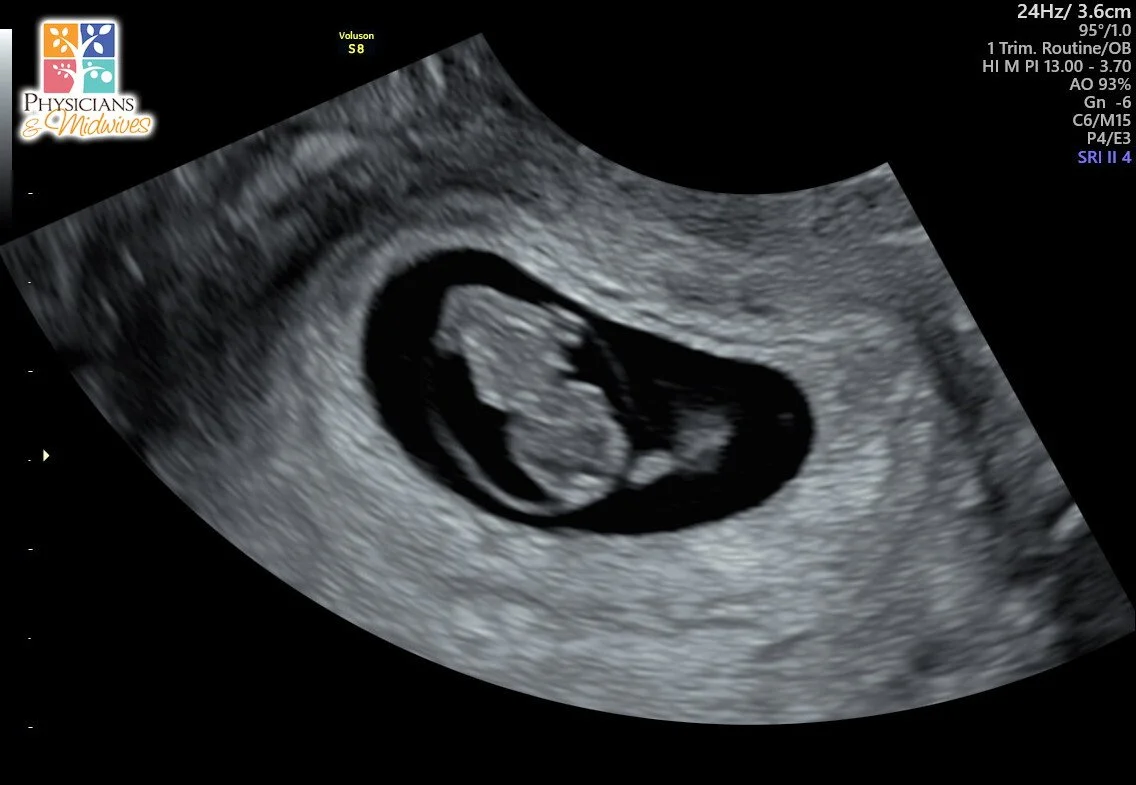

Been a while since I had the time to unload life’s blessings into blog form, but things have been honestly amazing for me and my family. Ash and I are expecting our second child. Phoenix is gonna be a big brother which is very exciting to see him in that role as he’s growing up so fast. We’re also getting him ready for Daycare, we’ve been blessed to have amazing Grandmothers to watch him as we go to work but now we want to socialize him a bit more and get him around kids his age. We took him on his first Airplane flight this past weekend to Atlanta to visit Ash’s Uncle. We had a blast, he wasn’t afraid at all and slept thru most of both flights there and back. We went to Skyzone, Lego Land, and to the Georgia Aquarium. A nice little quick getaway to test Phoenix’s flying capacity but I knew he’d like it the way he sleeps as soon as the car starts moving lol. Fatherhood has by far been the most rewarding gift as a man; learning how to be patient, gentle, and understanding on a whole new level. Married life isn’t much different than before we tied the knot, we’ve been locked in since the moment we met and I wouldnt have it any other way. Ash was/is an amazing wife before we even said our I do’s. Seeing her become a dedicated Mom while juggling work, life, and her passions in makeup is inspiring and I strive to be as compassionate of a person as she is. She gives me hope and unwavering support on my darkest of days. I pray my peers find someone to calm their soul the way she has soothed mine.